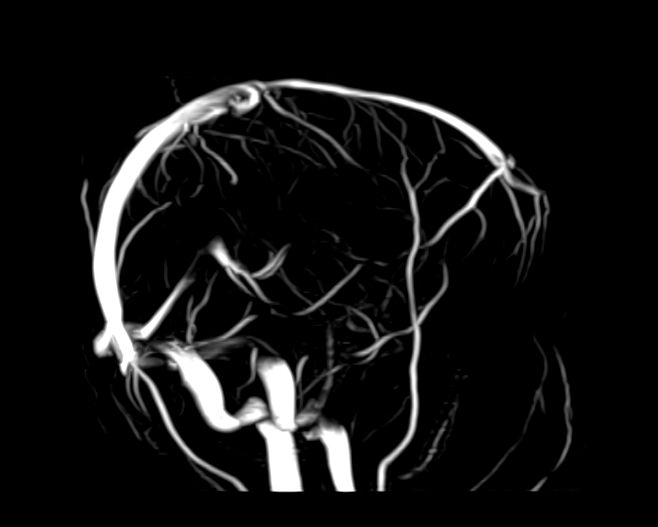

Магнитно-резонансная ангиография артериальной и венозной систем головного мозга позволяет получить трехмерное изображение сосудистой системы, кровоснабжающей центральную нервную систему, оценить анатомическое строение артерий и вен головного мозга и функциональные особенности кровотока.

С помощью внешнего магнитного поля томограф послойно сканирует структуры головного мозга, затем посредством компьютерных программ преобразует полученные данные в трехмерное изображение. При этом на снимке видна только сосудистая система без окружающих тканей. Таким образом, сканирование в режиме ангиографии позволяет визуализировать артерии и вены головного мозга без контрастирования.